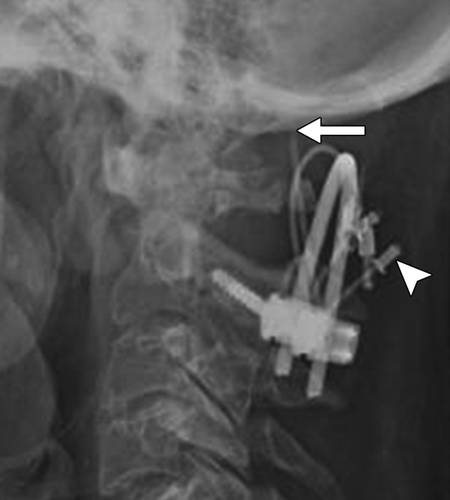

图9A-58岁的女性,颈椎融合手术。侧位X线照片显示结扎线连接器(箭头)分离,并向枕部移位(箭头)。

图9B-58岁的女性,颈椎融合手术,颈椎矢状CT图像和三维CT图像(插图)显示结扎线(箭头)穿入到了枕骨大孔。 颈椎不稳定是这种并发症的另一个后果。 箭头表示连接器。